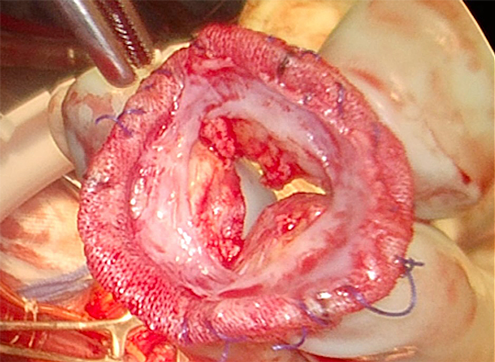

転院後より急激に循環不全が進行し,静脈脱血–動脈送血(VA)–体外式膜型人工肺(ECMO)導入を行った.同院でのTEEでは,構造的弁劣化による重症大動脈弁狭窄,生体弁周囲逆流を認めた.転院翌日に21 mm生体弁での大動脈基部置換術を施行した.術中所見として,生体弁は人工血管に直接縫合されており,生体弁と人工血管の縫合部の1/3周が破綻し,高度石灰化も認めた(Fig. 5).病理検査では高度石灰化を伴って線維化しており,培養は陰性であった.人工心肺からの離脱は困難であり,左室ベントを加えたECMO下に開胸帰室となった.

Pediatric Cardiology and Cardiac Surgery 41(2): 91-96 (2025)

Fig. 5 Extracted bioprosthetic valve

One-third of the circumference of the suture between the bioprosthetic valve and the graft had failed. Severe calcification of the bioprosthetic valve was also observed.